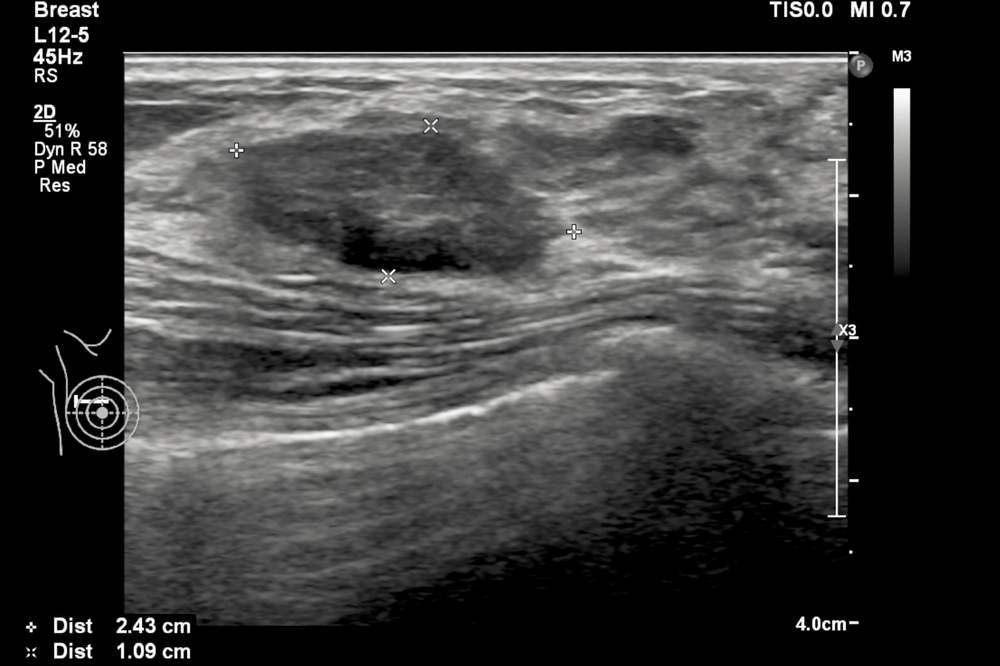

Badanie USG piersi przebiega bezboleśnie i trwa zazwyczaj około 15-20 minut. Pacjentka leży w wygodnej pozycji na plecach, a lekarz nakłada na skórę żel, który ułatwia przewodzenie fal ultradźwiękowych. Następnie, przy pomocy głowicy aparatu, specjalista przesuwa urządzenie po powierzchni piersi i interpretuje obraz widoczny na ekranie. USG umożliwia dokładne zlokalizowanie oraz ocenę wielkości i struktury wszelkich zmian w tkance piersiowej.

Skala BIRADS (Breast Imaging Reporting and Data System), opracowana przez American College of Radiology (ACR), to klasyfikacja używana w diagnostyce obrazowej piersi, głównie w mammografii i USG piersi. Umożliwia ujednolicenie opisów zmian i ułatwia podejmowanie decyzji o dalszym postępowaniu. Skala BIRADS od 0 do 6 ocenia ryzyko złośliwości zmian wykrytych w piersi, z zaleceniami dotyczącymi dalszej diagnostyki lub leczenia.